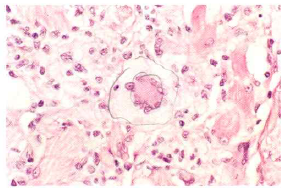

Q

What kind of cell is this? And what is the characteristic structure?

A

Langhans giant cells and Horseshoe arrangement of the nuclei.